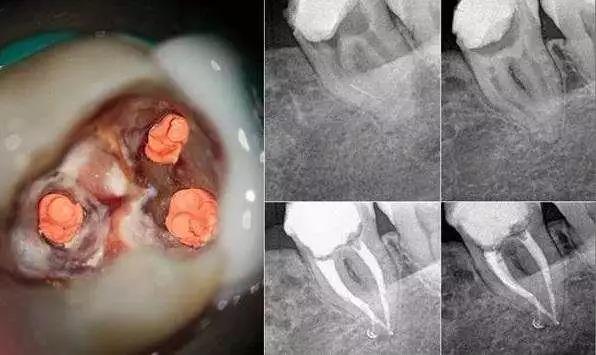

【病例】牙颈部龋致牙髓炎的治疗与修复-搜狐

图片尺寸1813x1053